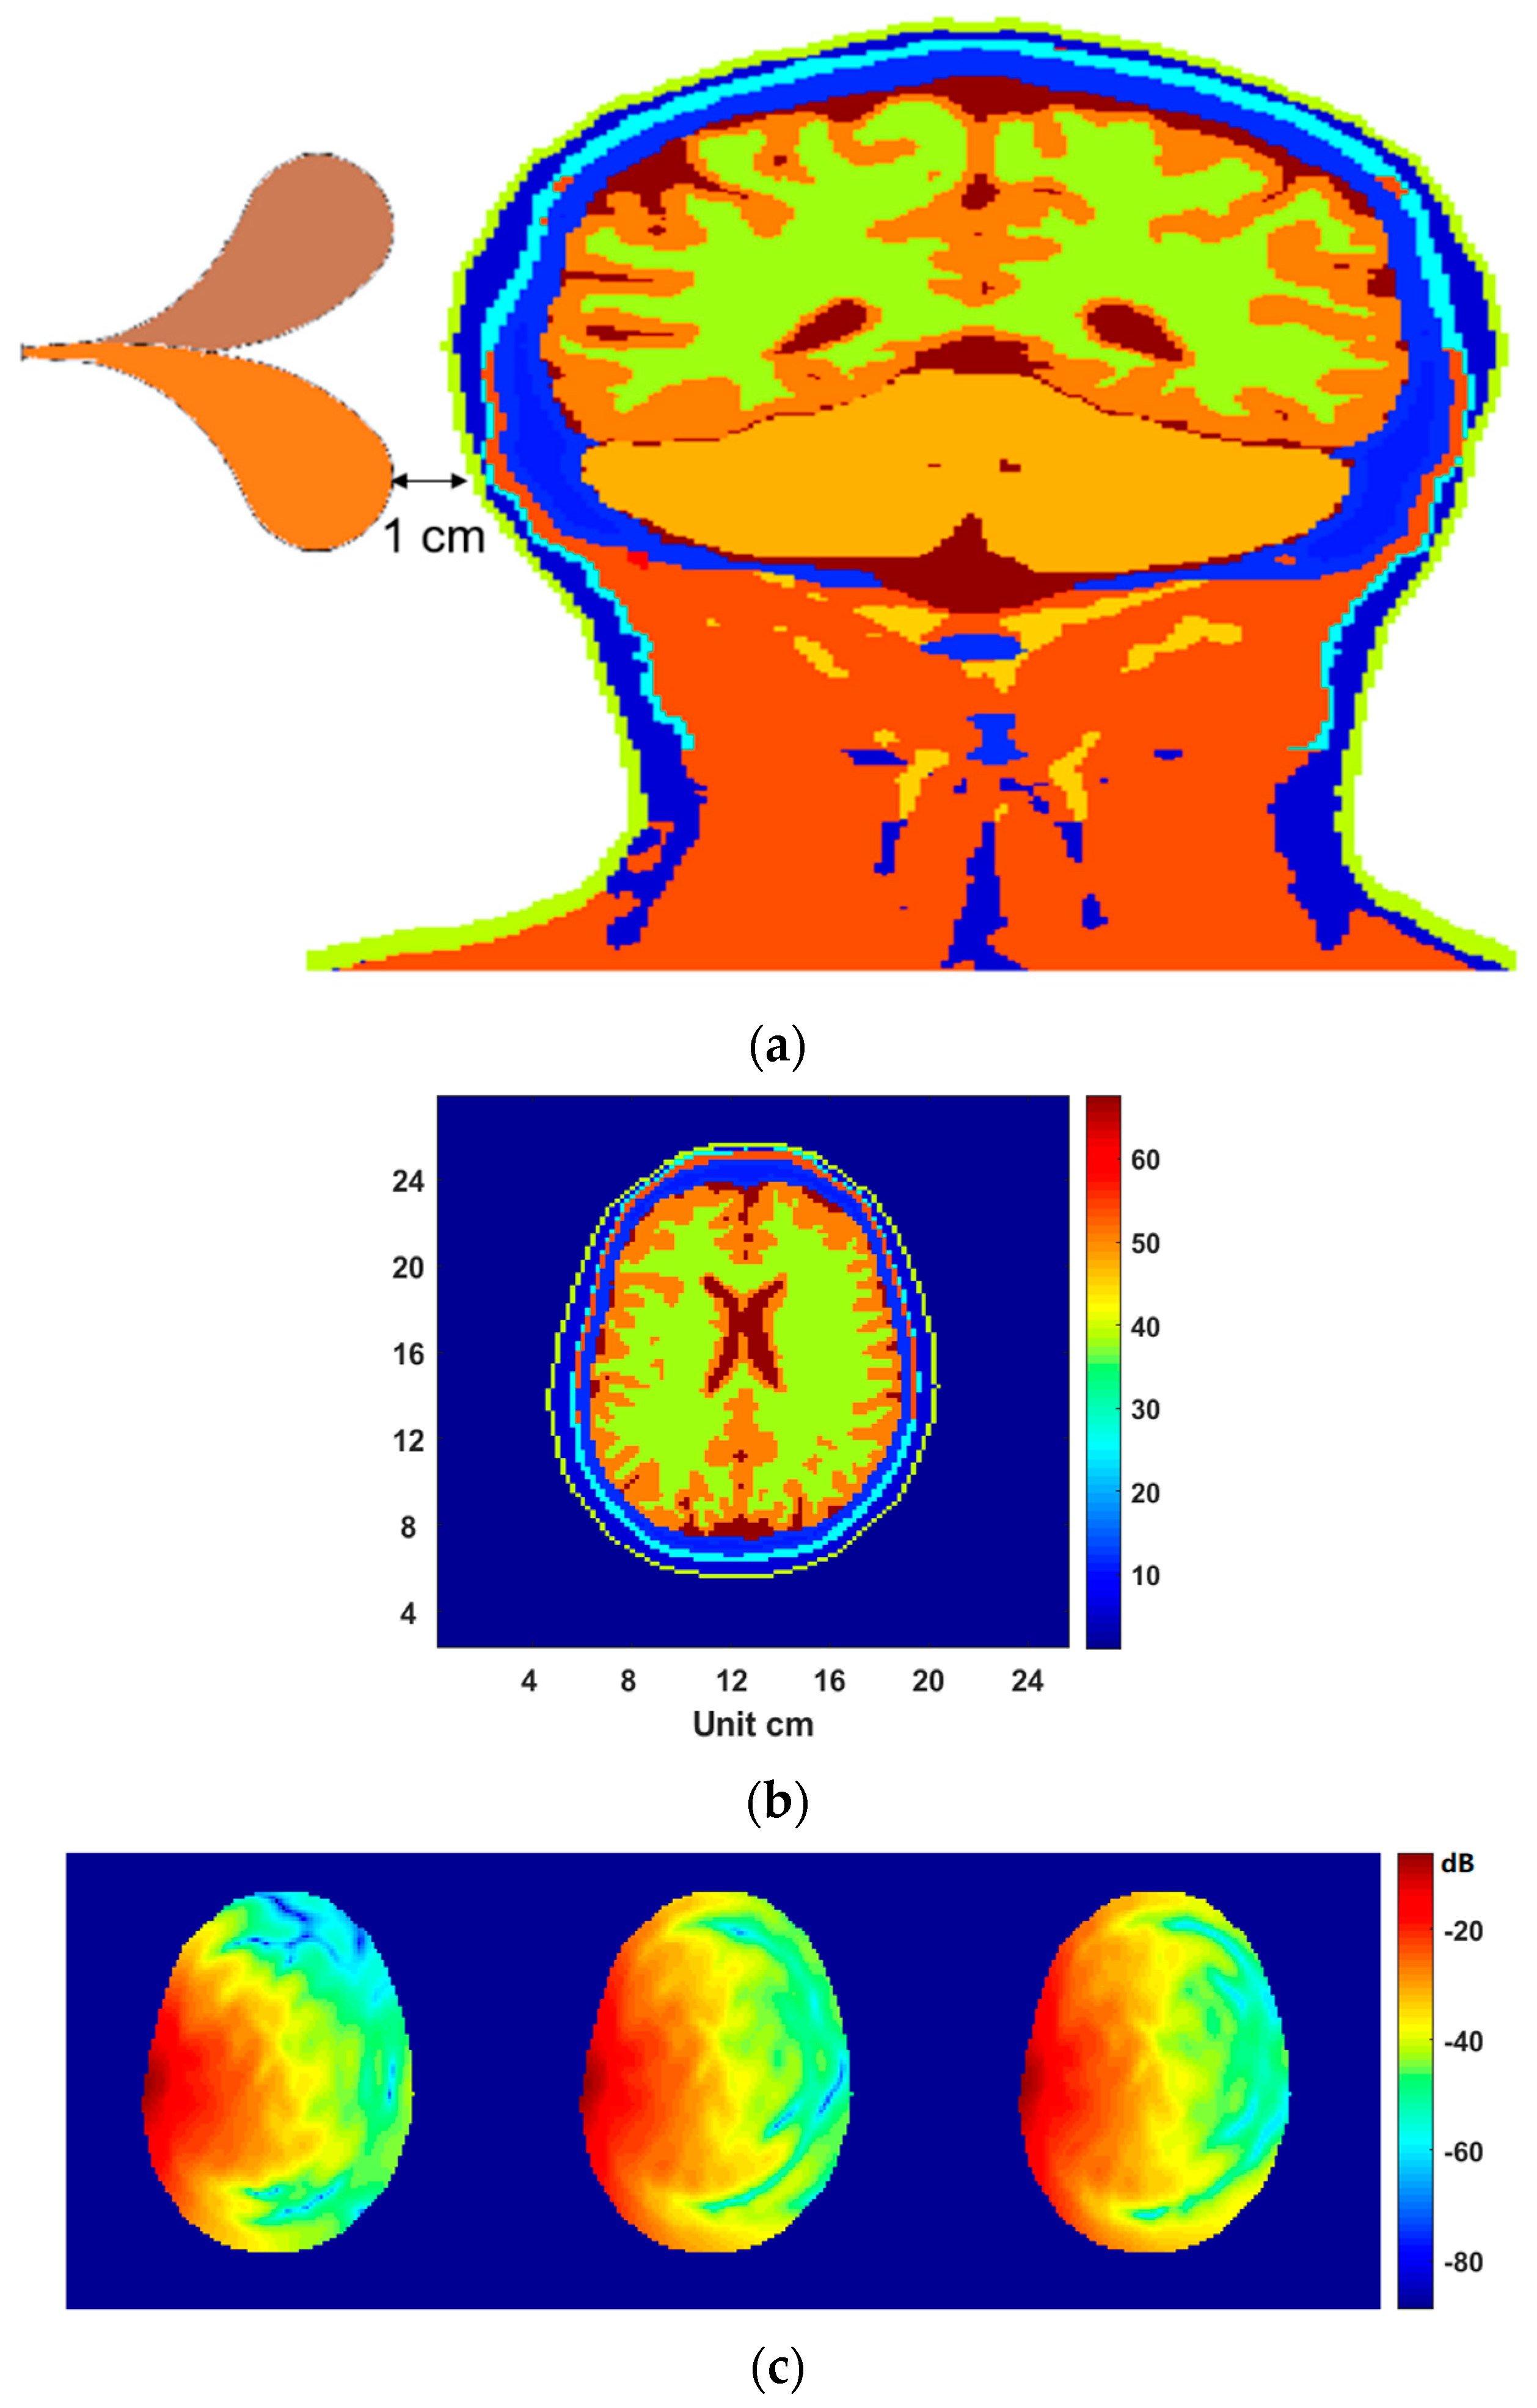

3.3. Electromagnetic Simulations